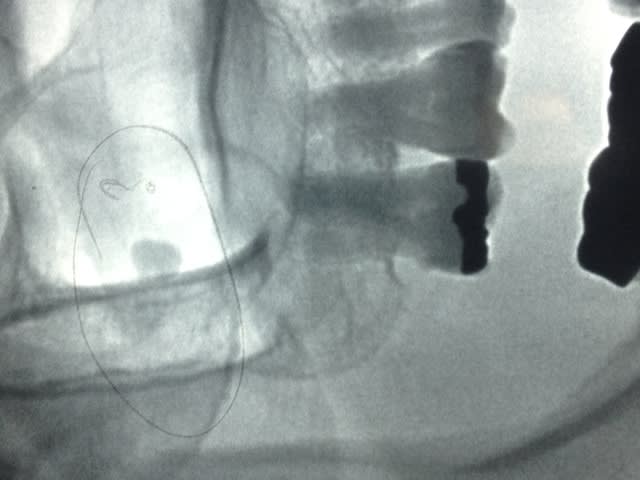

découverte fortuite sans aucune complication

Eh , bien quoi, ça peut aussi arriver à une 18 de se tromper de chemin...

Si elle ne pose aucun pb au sinus...

Oui. D'autant plus qu'on voit très bien un point d'interrogation sur la radio. Elle se demande pourquoi on lui cherche des noises !

tu sais c'est illogique qu'une dent de sagesse traîne au milieu du sinus (qui est une cavité).

tu es sûr que les deux sinus sont semblables? que le trait vertical que l'on semble voir en mésial ne montre pas une poche kystique.

je ferai bien un scanner pour en savoir plus